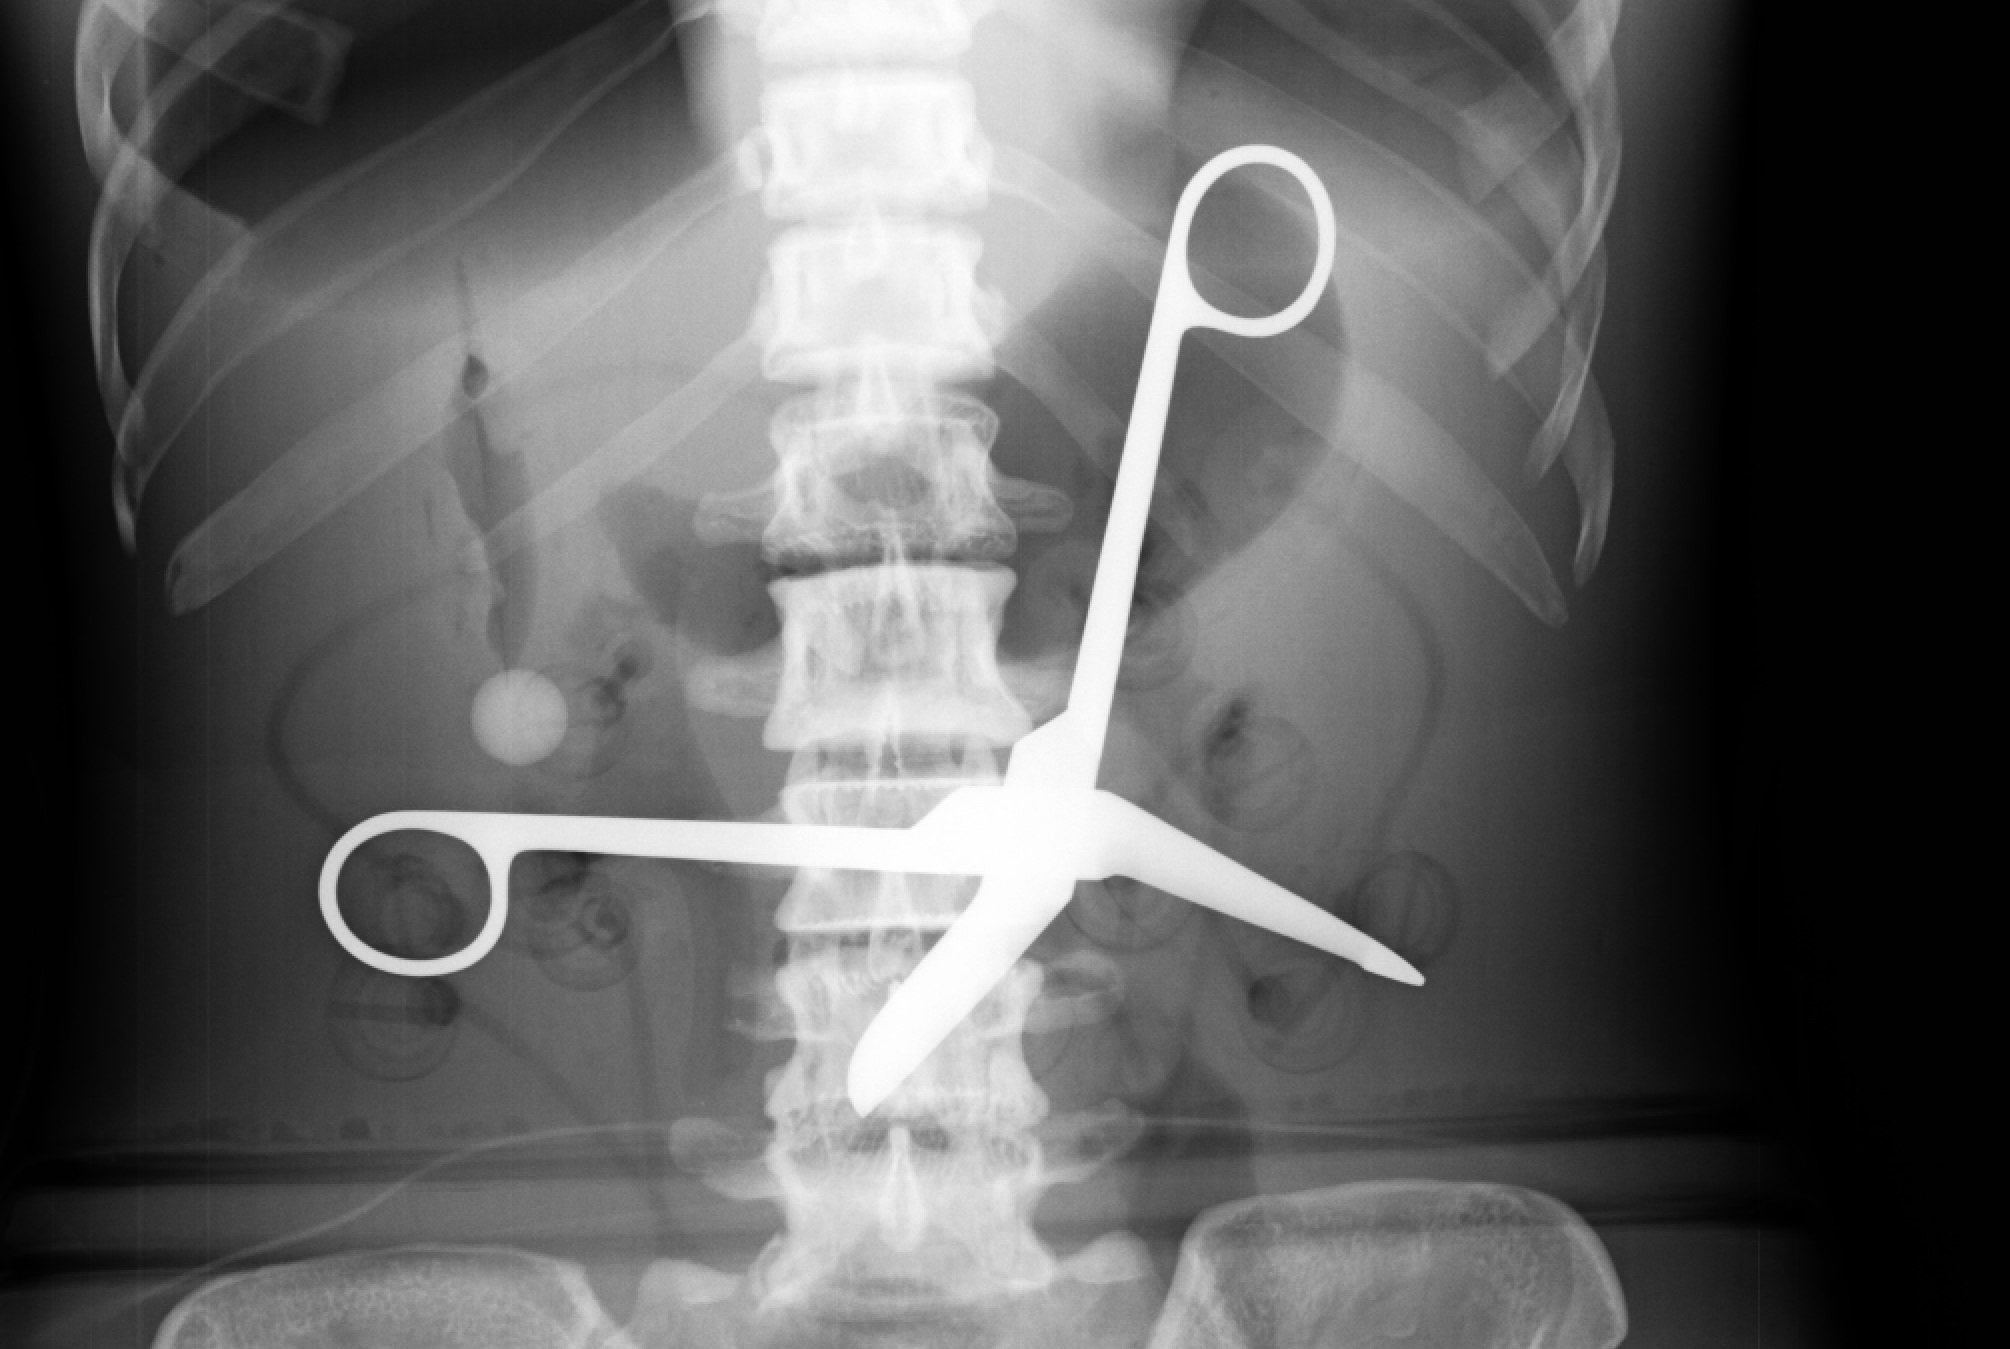

Professionals built this bridge:

This doctor was a professional (had to be to get their license):